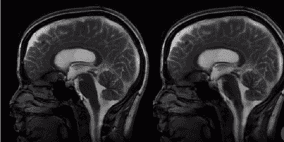

فيديو: هكذا ينبض الدماغ مع القلب..لقطات مذهلة